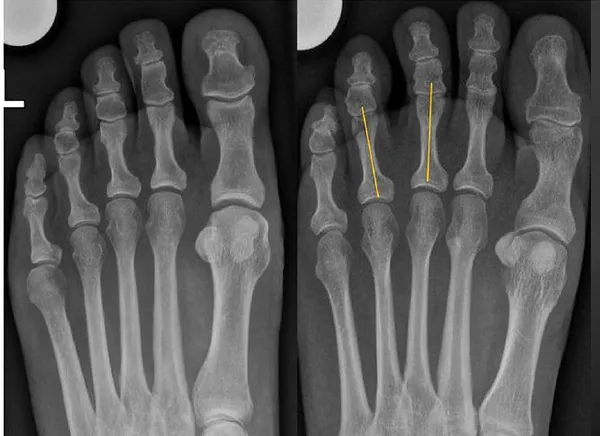

As radiografias dos pés com carga costumam ser solicitadas nos casos de metatarsalgia, principalmente para afastar outros diagnósticos, como fratura. Embora o RX normal não exclua o diagnóstico de neuroma de Morton, um sinal conhecido como "sinal do V" ou da "sinal da saudação de Vulcano", em que as falanges dos 2º e 3º ou dos 3º e 4º dedos ficam com aspecto divergente em vez de paralelo é considerado um sinal indireto bastante específico de neuroma de Morton. Isso ocorro pelo efeito de massa exercido pelo neuroma de Morton que promove um afastamento das falanges do respectivo espaço interdigital. Seria o equivalente radiográfico ao sinal de Sullivan, em que o afastamento entre os dedos é visto no exame físico. Veja imagem acrescentada no final do texto.

Radiografias com carga na incidência dorsoplantar de indivíduo sem neuroma de Morton (à esquerda), onde as falanges são praticamente paralelas, e em paciente com neuroma de Morton à direita, mostrando o sinal da saudação de Vulcano, onde as falanges do 3º e 4º dedos tem aspecto divergente (linhas amarelas). Modificado de The Vulcan salute sign: a non-sensitive but specific sign for Morton's neuroma on radiographs. Skeletal Radiol. 2022 Mar;51(3):581-586.